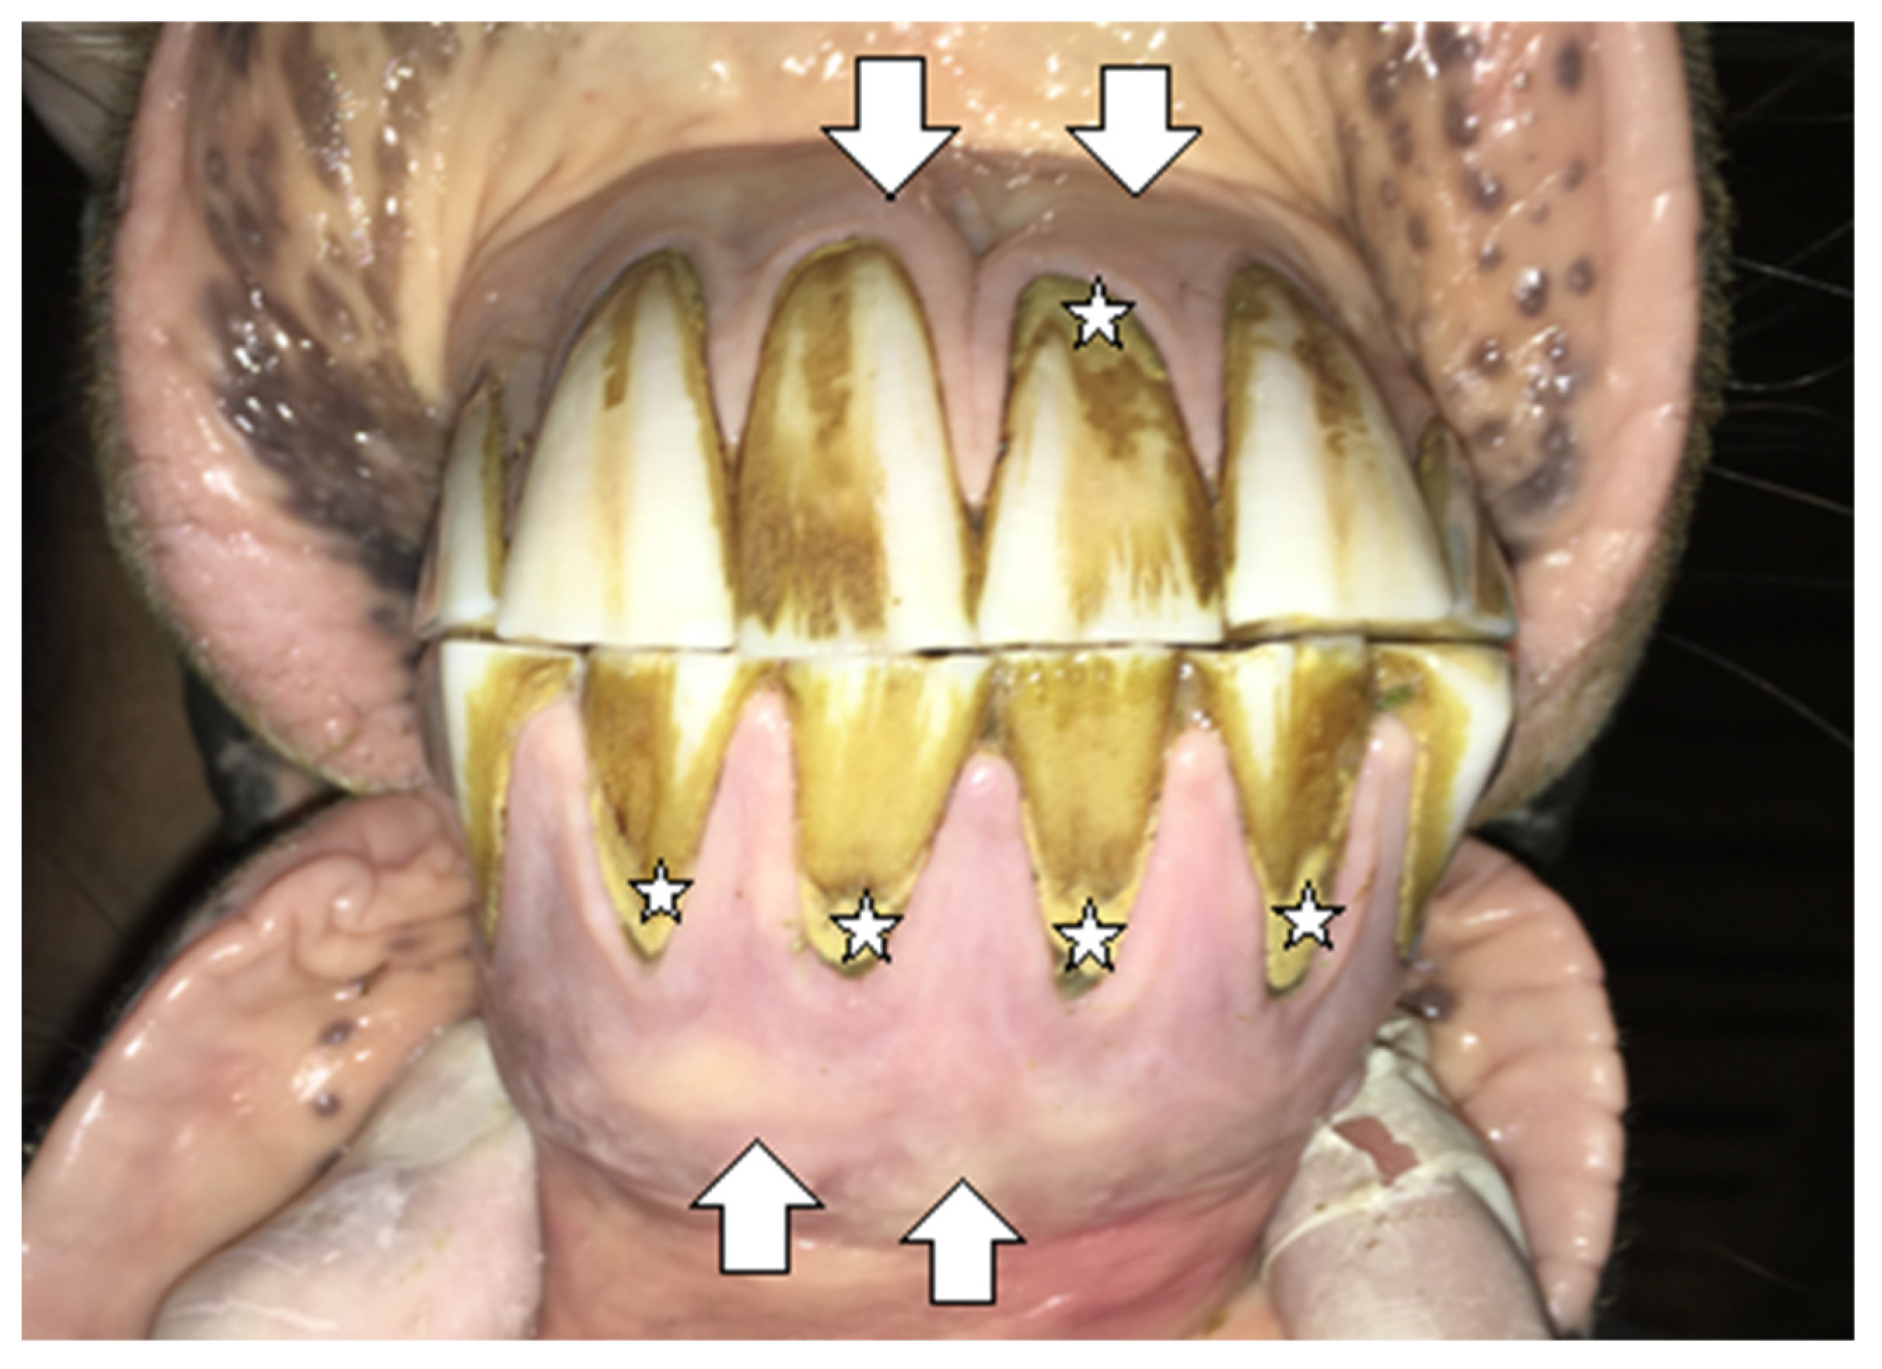

2.1.1. Case 1

2.1.2. Case 2